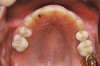

Figure 5c  Note lack of alveolar development from congenitally missing Nos. 24 and 25. Surgical procedures after 5 months of orthodontic alignment included single-tooth osteotomies Nos. 6 to 11 and Nos. 21 to 28 and buccal corticotomies on all other teeth. Anchorage plate was stabilized to piriform rim.

Figure 5c

Figure 5d  Note lack of alveolar development from congenitally missing Nos. 24 and 25. Surgical procedures after 5 months of orthodontic alignment included single-tooth osteotomies Nos. 6 to 11 and Nos. 21 to 28 and buccal corticotomies on all other teeth. Anchorage plate was stabilized to piriform rim.

Figure 5d

Figure 5e  Anchorage plate was stabilized to piriform rim (E through H). Final result 12 months postsurgery (F). There is significant lateral dentoalveolar expansion of arches and alveoloskeletal correction in maxillary and mandibular anterior regions. Alveolar bone volume was increased in lower anterior to create optimal implant sites and establish ideal interincisal function and stability.

Figure 5e

Figure 5f  Anchorage plate was stabilized to piriform rim (E through H). Final result 12 months postsurgery (F). There is significant lateral dentoalveolar expansion of arches and alveoloskeletal correction in maxillary and mandibular anterior regions. Alveolar bone volume was increased in lower anterior to create optimal implant sites and establish ideal interincisal function and stability.

Figure 5f